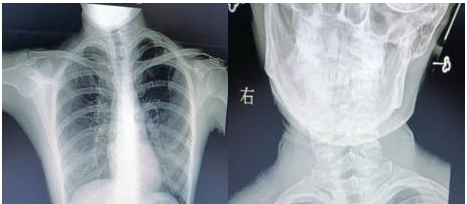

通訊員楊航報(bào)道:18歲的小唐(化名)是個(gè)笑容明媚的在校大學(xué)生,平時(shí)無論是坐著,站著,走路,脖子就不由自主的偏斜,這種情況讓小唐很困擾。多年來,小唐父母帶她去多家醫(yī)院保守治療,效果還是不理想,經(jīng)過多方打聽,慕名來到衡陽市中心醫(yī)院骨科一區(qū)求醫(yī)。錢軍副主任接診后詳細(xì)詢問病情,結(jié)合相關(guān)輔助檢查,診斷小唐(化名)是“先天性肌性斜頸”。

近日,在蘇光輝主任帶領(lǐng)下,制定完美的手術(shù)方案,與麻醉科及手術(shù)室的共同配合下,順利進(jìn)行了左側(cè)胸鎖乳突肌攣縮胸骨頭+鎖骨頭切斷+胸鎖乳突肌黏連松解+切口美容縫合手術(shù)。術(shù)后經(jīng)過精心護(hù)理,患者恢復(fù)良好,患者及家屬對手術(shù)效果非常滿意,現(xiàn)已佩戴支具出院。

錢軍副主任介紹,“先天性肌性斜頸”最常見的原因是患兒出生前胎位不正,頭頸部扭曲,致頸肌肉供血發(fā)生障礙,肌肉變形、逐漸攣縮,引起頸部兩側(cè)肌肉平衡失調(diào),使頭部偏向變攣縮的一側(cè),形成頭頸側(cè)斜。